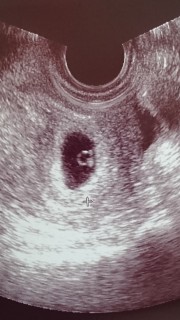

1週間前に胎嚢を確認し、ひとまず安心してましたが、1日だけ茶オリがあったので、やはり心拍確認出来るまでゎ不安でした。今日自分の心臓の脈よりも早い心拍をみて、元気に育ってくれてるなーと感激しました。赤ちゃんの大きさゎ5.7mmだって☆また病院にいったら、投稿します^^